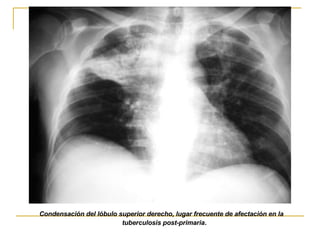

TBC SECUNDARIA Mas común en los adultos área de afectación mas frecuente son los lob. Sup. y tendencia bilateral Cavitación frecuente(37-75%)por necrosis Ausencia de linfoadenopatías

Condensación del lóbulo superior derecho, lugar frecuente de afectación en la tuberculosis post-primaria .